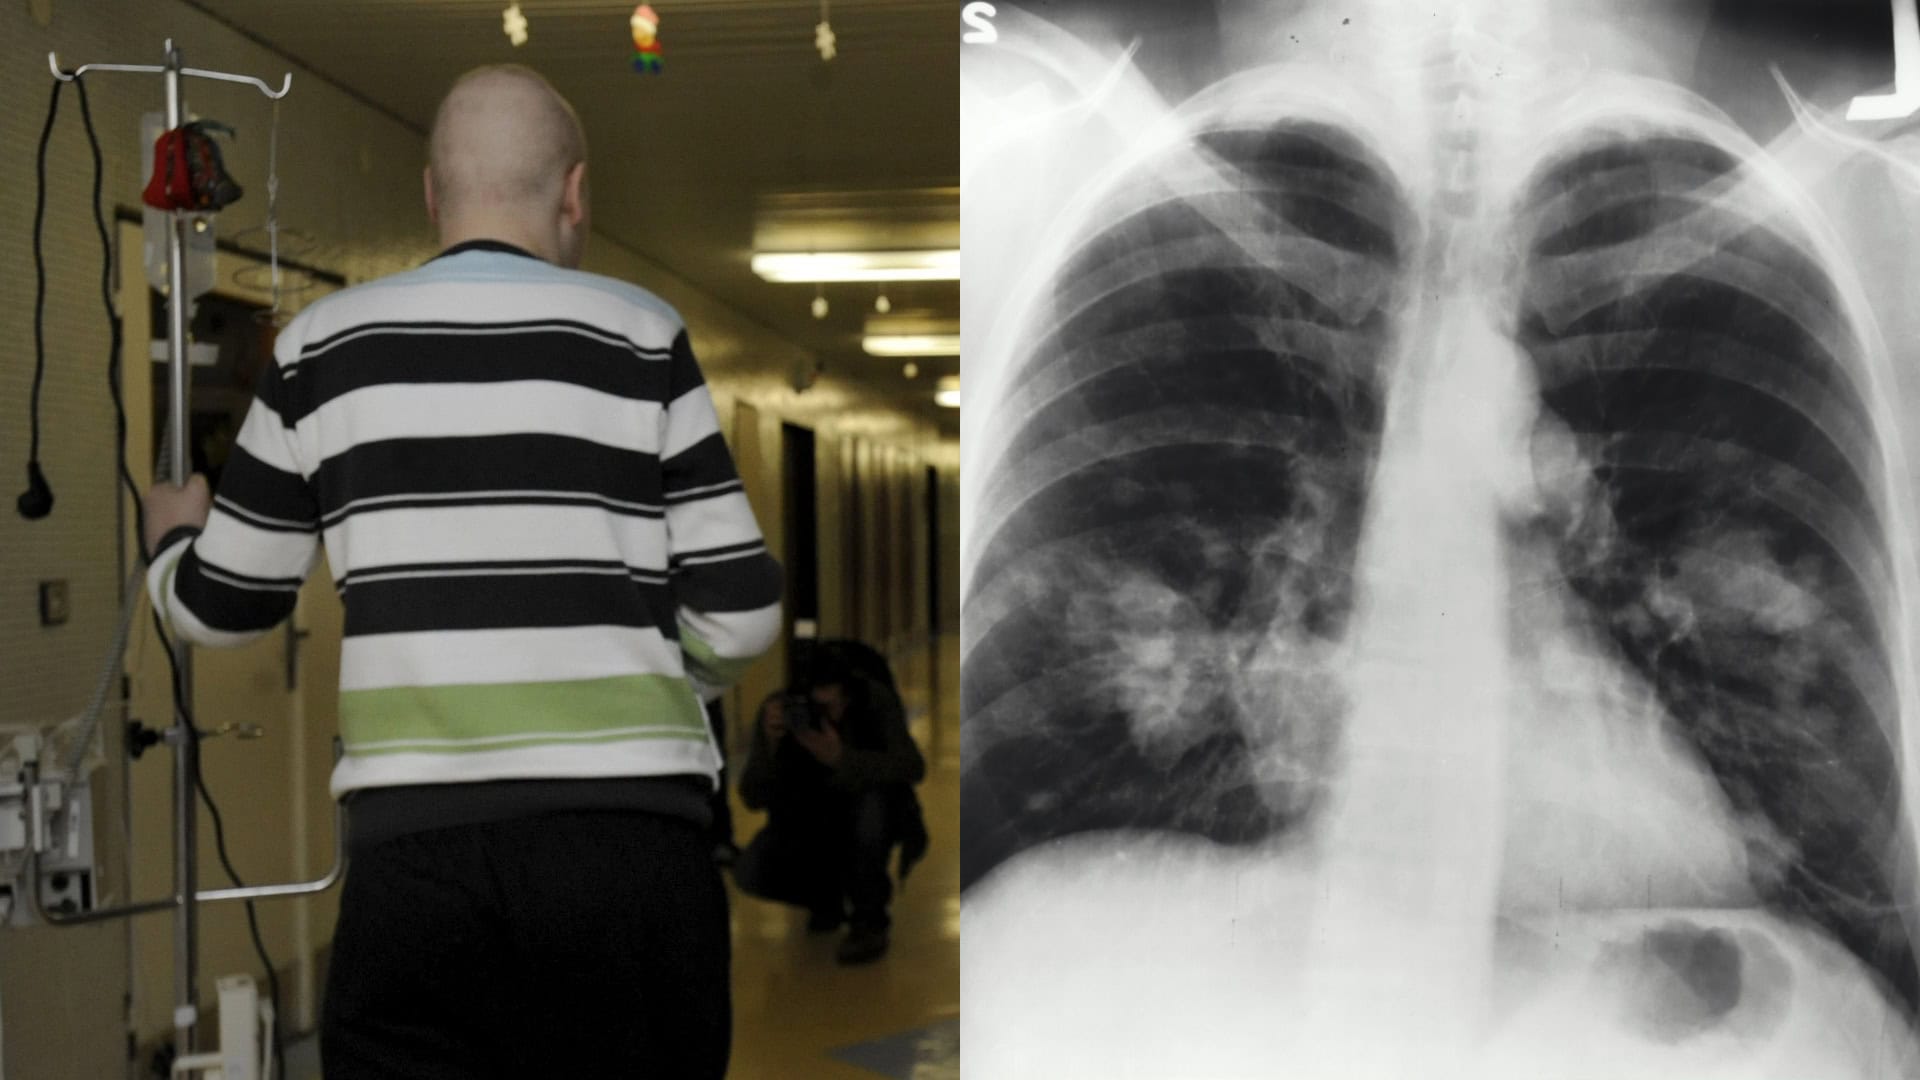

Ďalšie časté druhy rakoviny zahŕňajú rakovinu pľúc, ktorá je najčastejšou príčinou úmrtia na toto onkologické ochorenie. Fajčenie a pasívne fajčenie sú hlavné rizikové faktory. Na rakovinu pľúc zomrie na Slovensku každé štyri hodiny jeden človek, čo je ročne takmer tritisíc úmrtí. Slovensko má tiež, ako je spomenuté v úvode článku, vysokú incidenciu rakoviny hrubého čreva a konečníka.